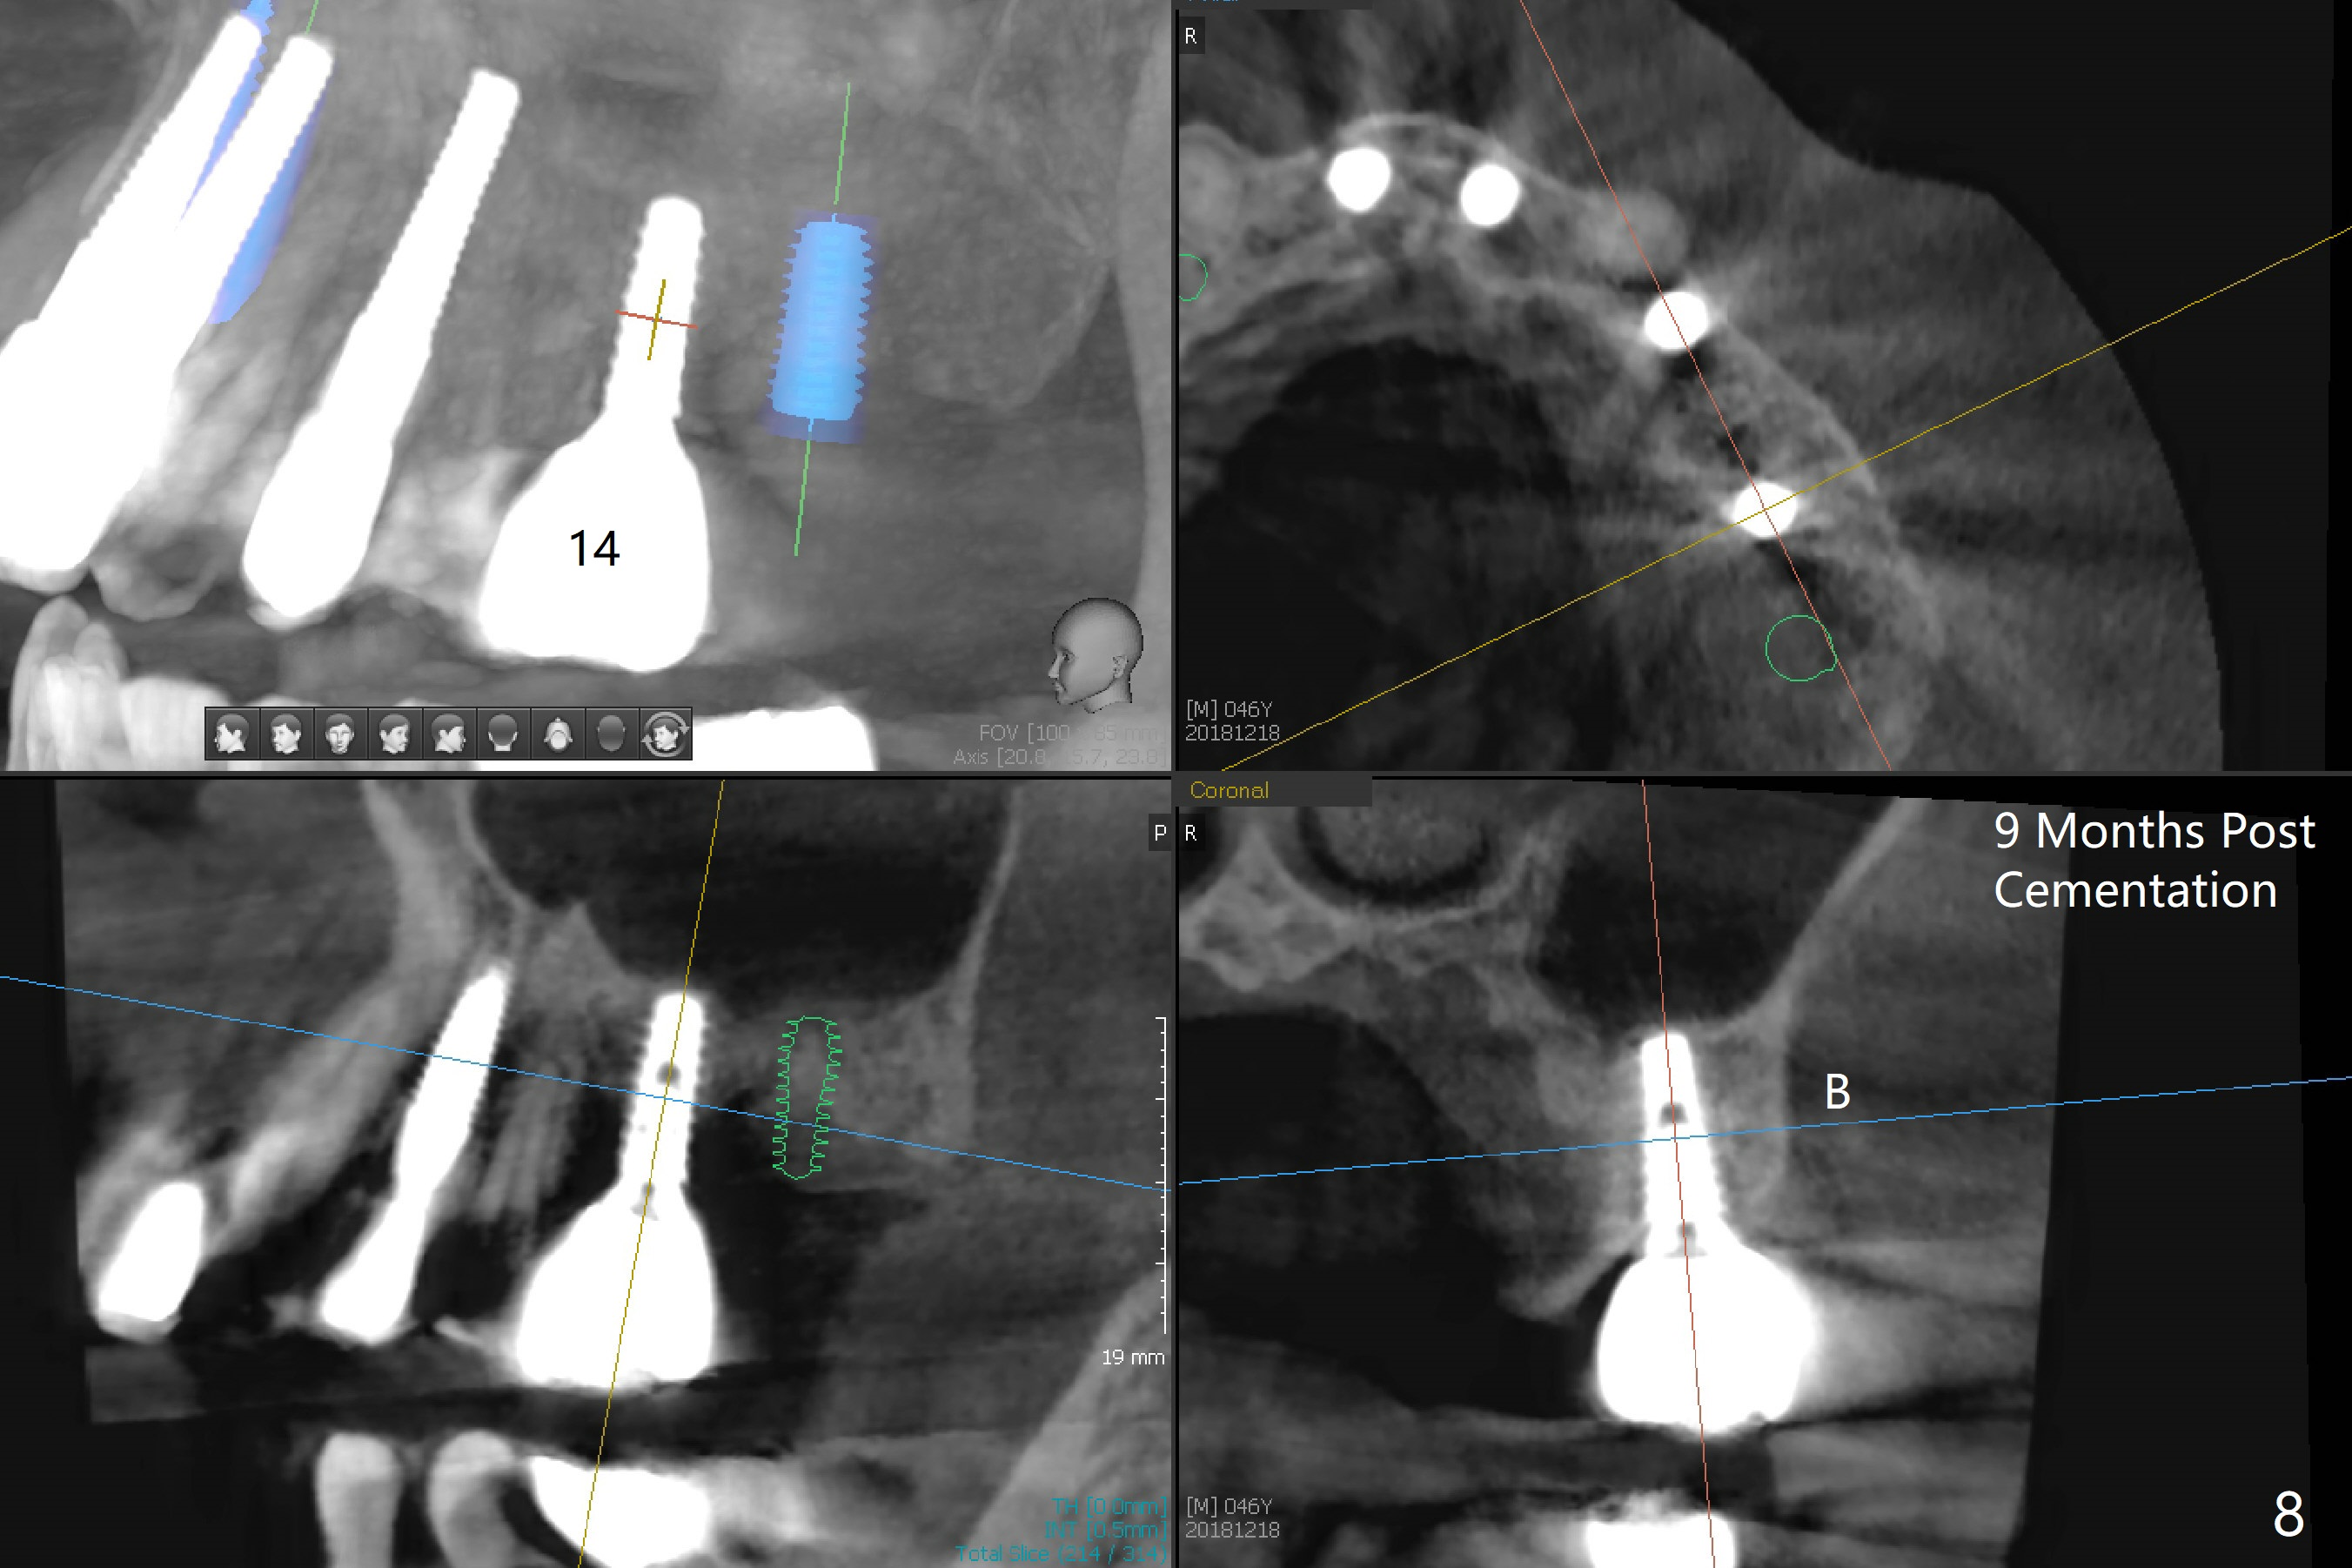

The ridge over the mobile tooth #14 is wide, suggesting bruxism pathogenesis (Fig.1). In spite of calculus over the roots of the extracted tooth (Fig.2), the septum remains. Osteotomy is initiated in the palatal slope of the septum (Fig.3,3' red dashed line). A 4.3 mm Magic Drill (MD) cannot bite into the bone probably because of the slope. Sequential osteotomy has to be done, starting with the smallest MD until 4.8 mm one. A 5x9 mm dummy implant is placed with 50 Ncm (Fig.4). To place 5x11 mm IBS implant (Fig.5), 5.3 mm MD has to be used; prior to implant placement, sinus lift is accomplished with mixture of autogenous bone and Vanilla graft (white *); more allograft (black *) is placed around the implant before insertion of a 6x5.7(3) mm abutment. More allograft is placed around the abutment (Fig.6 *) prior to an immediate provisional fabrication. The grafted bone appears to become the native bone, although at the low density, 6.5 months postop (Fig.7). The implant at #14 appears to have been placed in the middle of the alveolus buccopalatally (Fig.8).